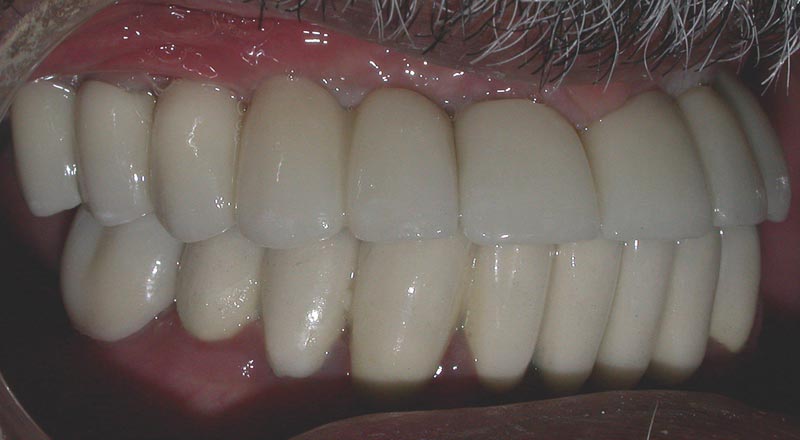

After